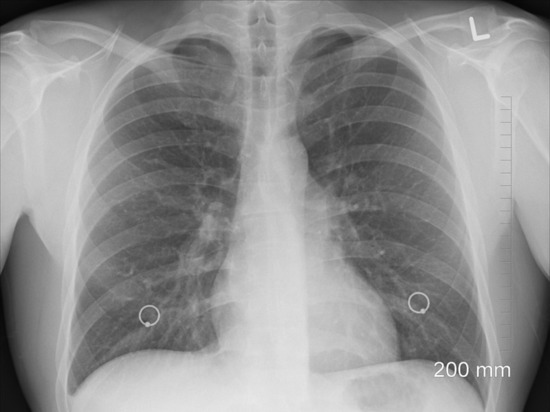

фото: pixabay.com